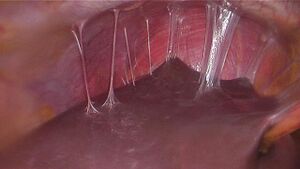

Fitz-Hugh–Curtis syndrome with perihepatic adhesions following a chlamydia infection

PID can cause scarring inside the reproductive system, which can later cause serious complications, including chronic pelvic pain, infertility, ectopic pregnancy (the leading cause of pregnancy-related deaths in adult females), and other complications of pregnancy.[16] Occasionally, the infection can spread to the peritoneum causing inflammation and the formation of scar tissue on the external surface of the liver (Fitz-Hugh–Curtis syndrome).[17]

Laparoscopy can visualize "violin-string" adhesions, characteristic of Fitz-Hugh–Curtis perihepatitis and other abscesses that may be present.[23]